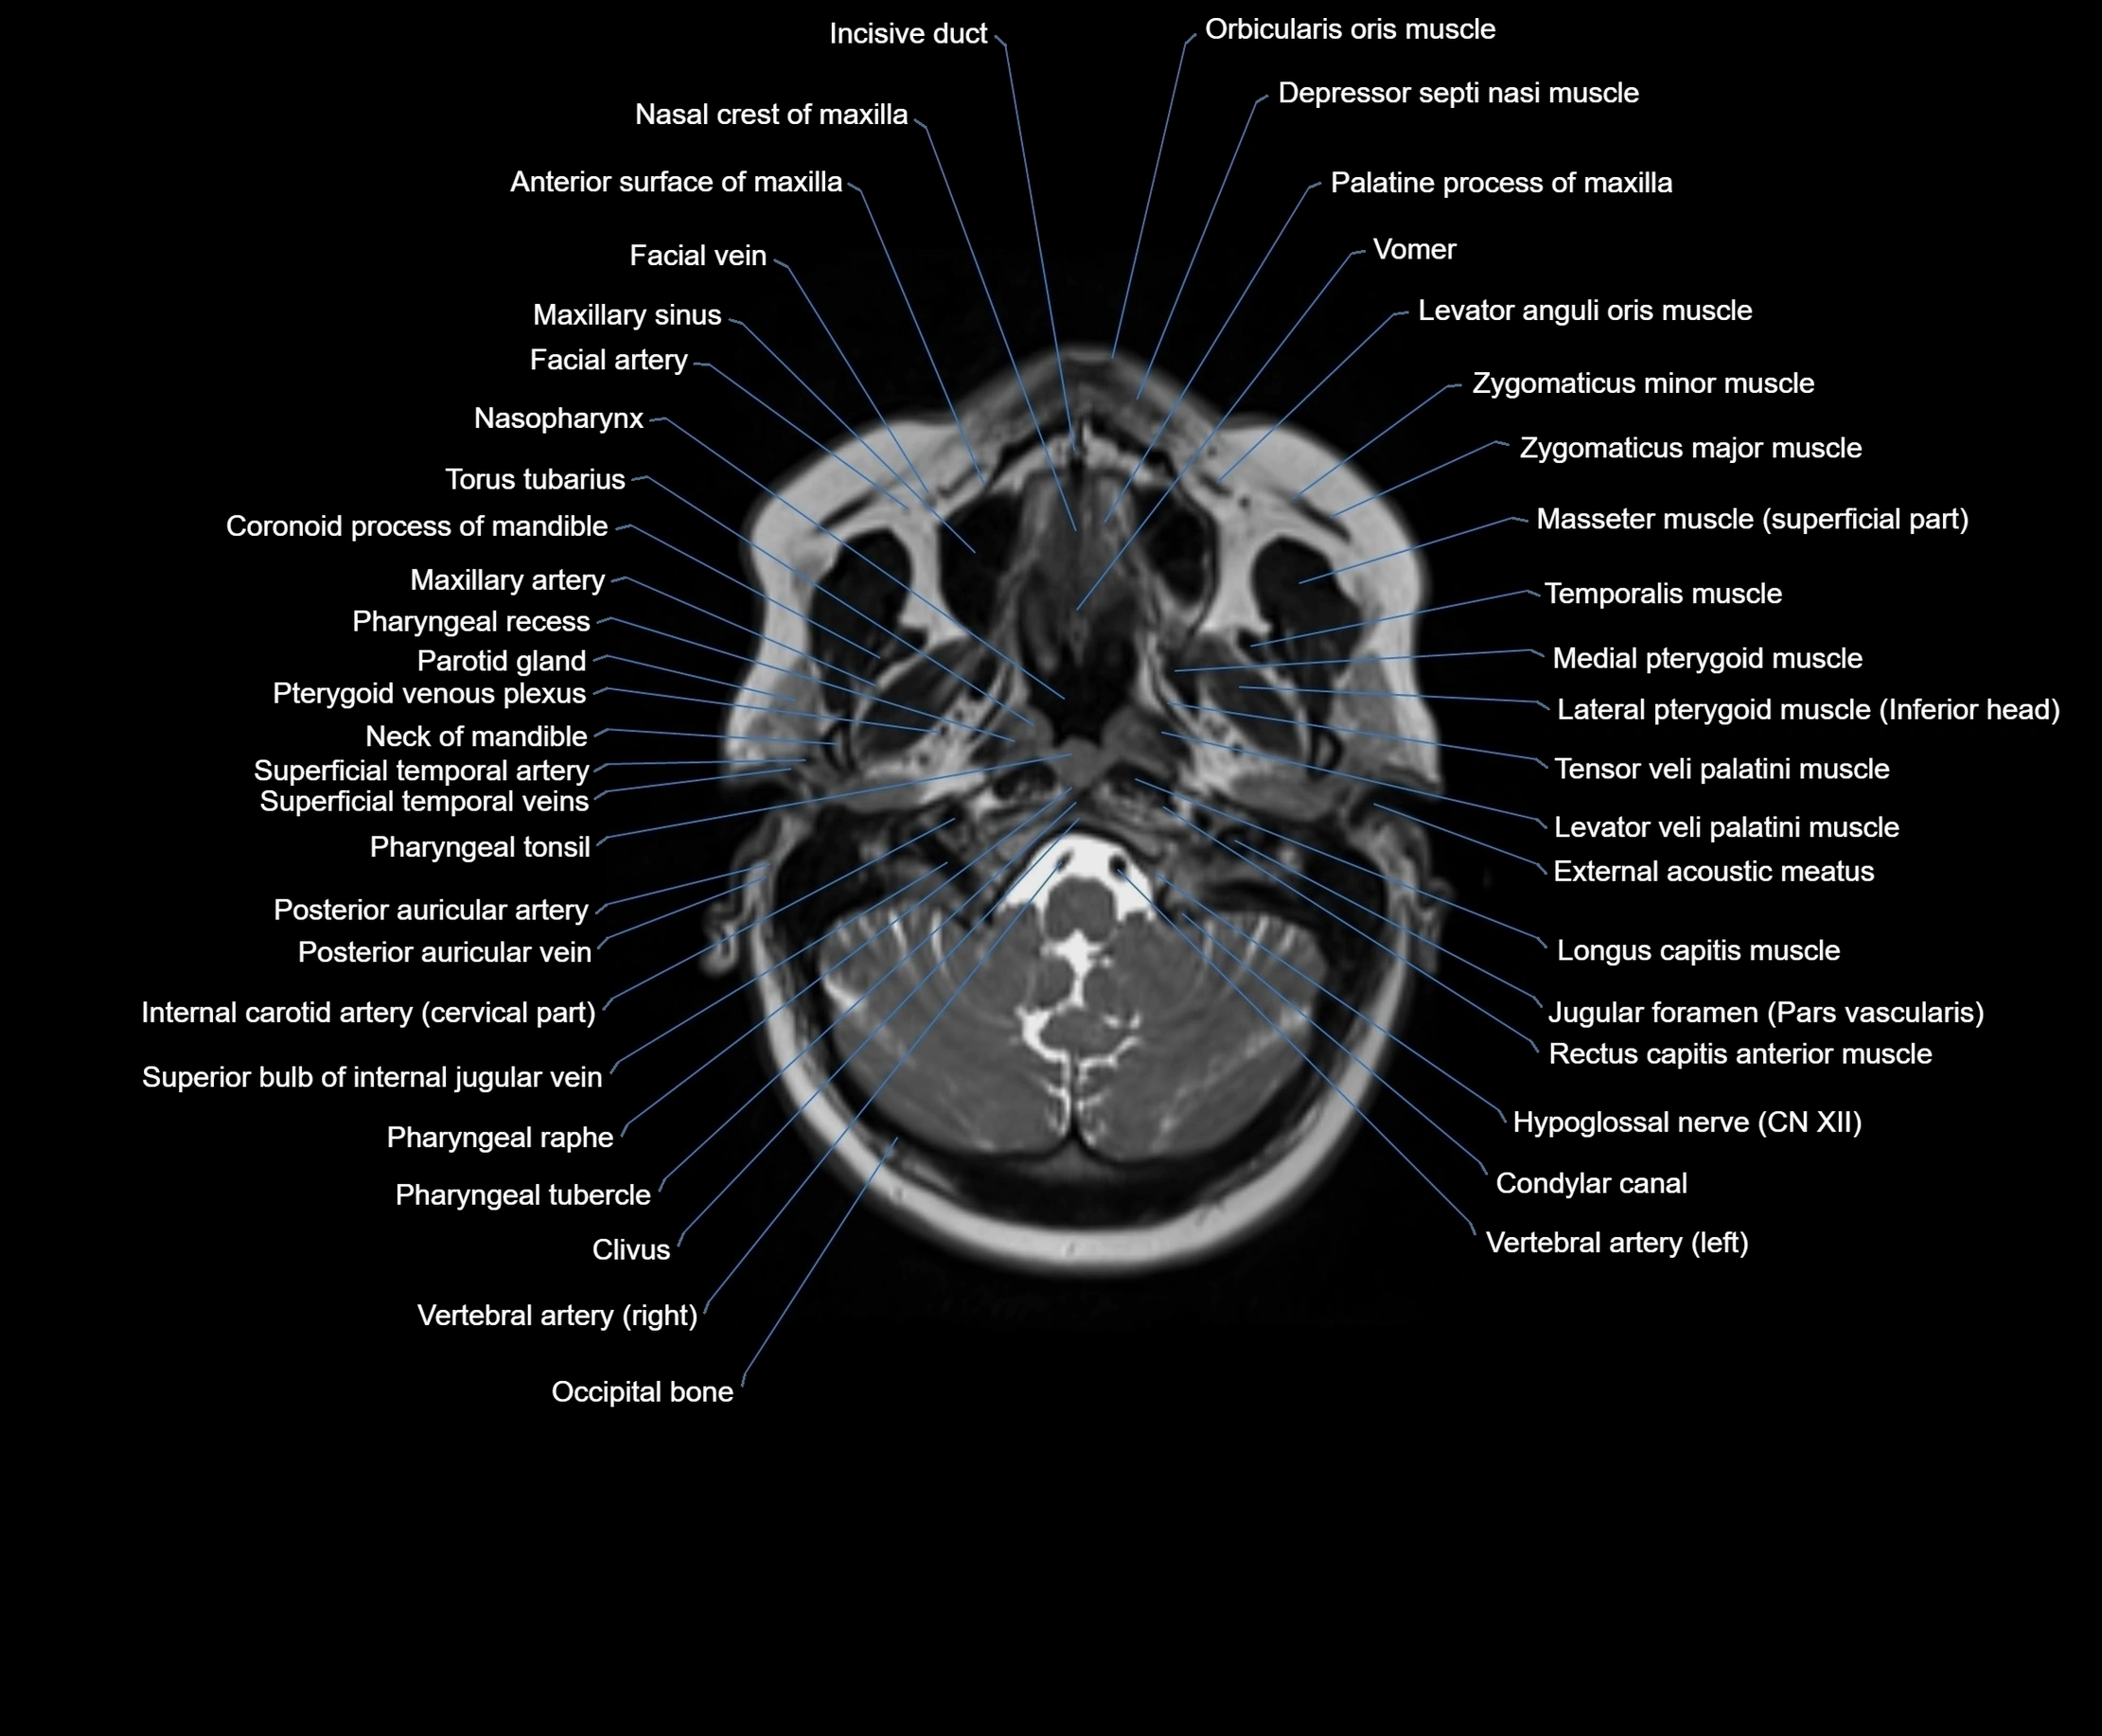

MRI images